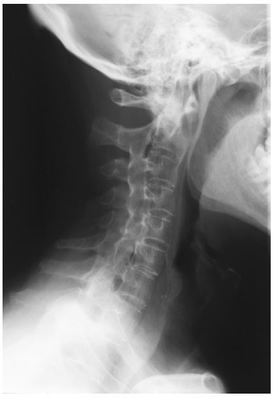

A 54-year-old man presents with neck pain. Examination reveals a limited range of movement of the neck. Which feature on the X-ray shown above best explains the limited range of movement?

Answer

• A. Zygoapophyseal joint fusion.

• B. Diffuse disc degeneration.

• C. Upper cervical spine instability.

• D. Calcification of the posterior longitudinal ligament.

• E. Diffuse idiopathic skeletal hyperostosis.